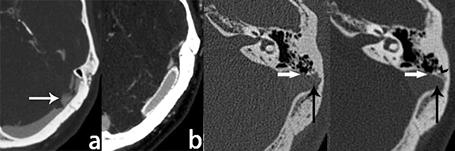

本中心自主研制了分辨尺度达0.05毫米的(国际最高)的CT设备,对于搏动性耳鸣骨质病因的精确评估较其他高端CT设备具有显著优势,包括骨壁裂缺、半规管裂、耳硬化症等。

图10.骨壁重建手术前后的术中图像和CT图像